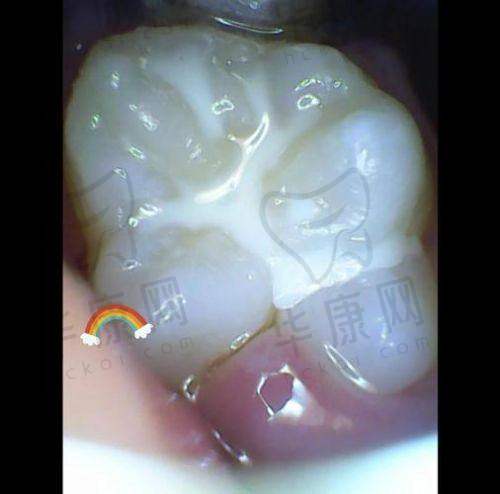

在西昌,家长们都在关注孩子的口腔健康,而西昌春城口腔推出的儿童窝沟封闭58元起的活动,无疑成为了热门选择。儿童窝沟封闭是预防龋齿的有效手段,那么西昌春城口腔在这一项目上有怎样的价格优势和特色呢?下面就为您详细介绍。

西昌春城口腔是西昌市规模较大的高端数字化齿科机构。它始终坚持价格透明、合理定价的策略,为患者提供高性价比的口腔医疗服务。医院拥有精良的数字化设备,在进行儿童窝沟封闭时,能够更精细地诊断孩子牙齿的状况,确保封闭成效。例如,通过数字化影像技术,可以清晰地看到牙齿窝沟的深浅和形态,从而为孩子制定更合适的封闭方案。